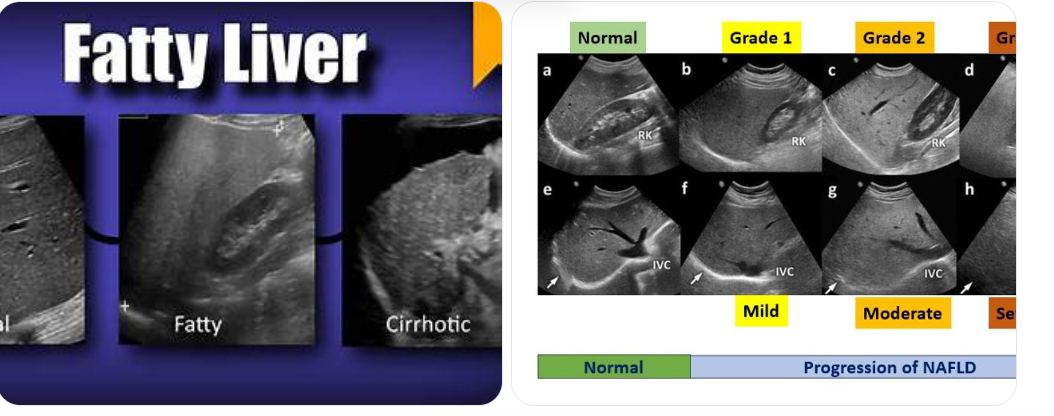

This Is Not an Alcoholic’s Liver

Non-alcoholic fatty liver disease is now one of the most common metabolic conditions worldwide.

It affects people who eat “healthy,” exercise regularly, and rarely drink alcohol. Fat accumulates silently in the liver, disrupting insulin signaling, increasing inflammation, and raising long-term risk for cardiovascular disease and cognitive decline.

Most people feel nothing until damage is advanced.

The absence of pain does not mean the absence of disease.

- Fatty liver disease , often discovered incidentally on ultrasound, with no discomfort until fibrosis develops